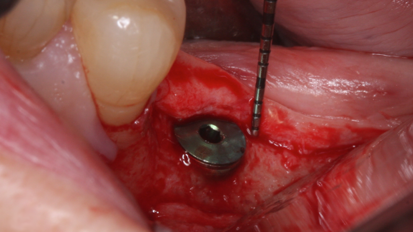

Historically, when a patient’s dental condition reached a state of total tooth loss, treatment was limited to a complete denture with no hope of ...